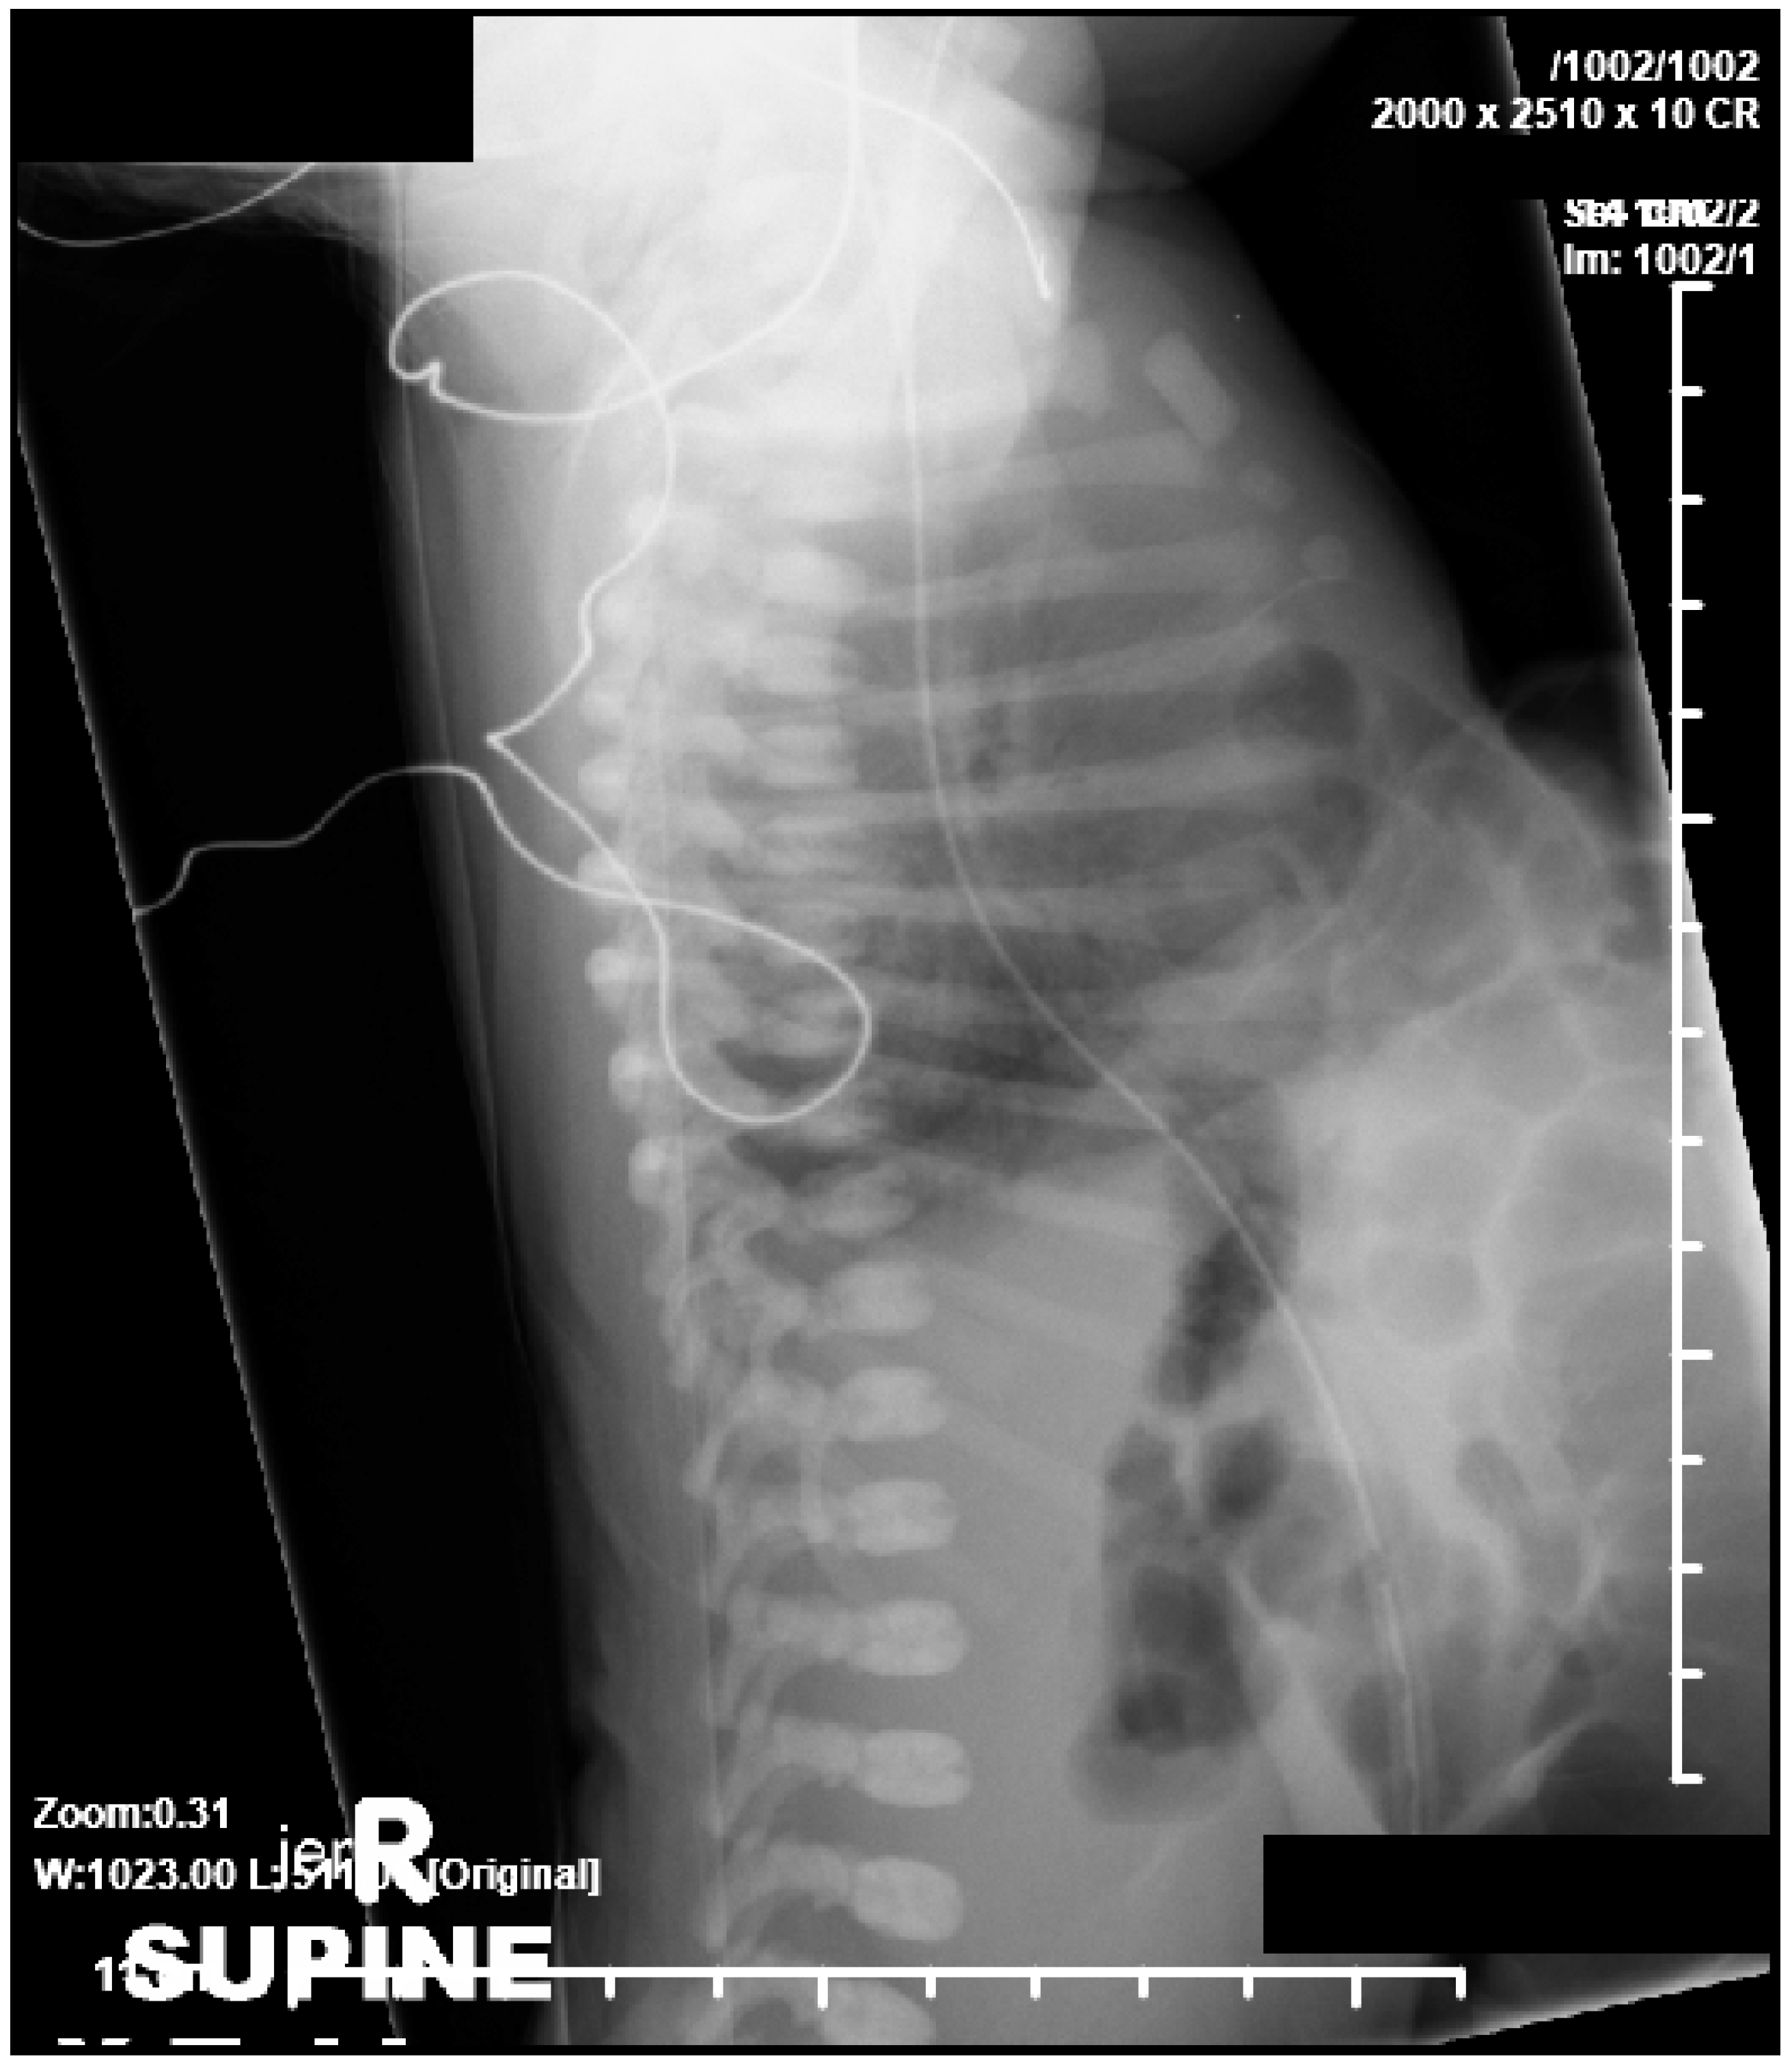

2.1. Case 1

2.2. Case 2